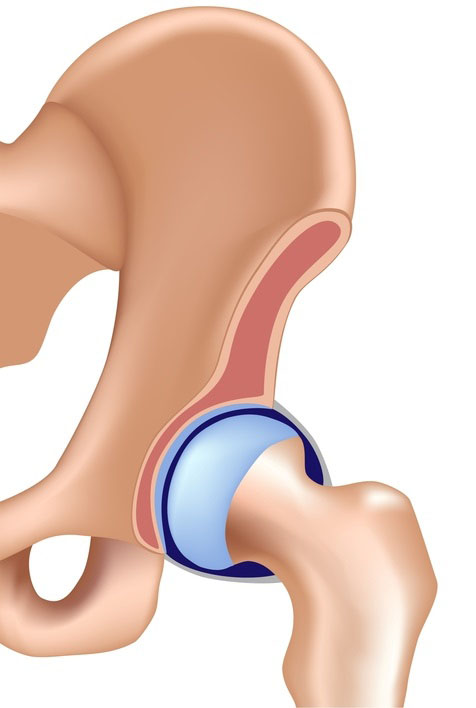

Hüftgelenkersatz – Totalendoprothese Hüfte (TEP)

Warum brauche ich eine neue Hüfte?

Aus verschiedenen Gründen kann es in der Hüfte zu Knorpelverschleiß (Arthrose) kommen, der die Gelenkflächen negativ verändert.

gesunde Hüfte

Hüfte mit Arthrose

gesunde Hüfte